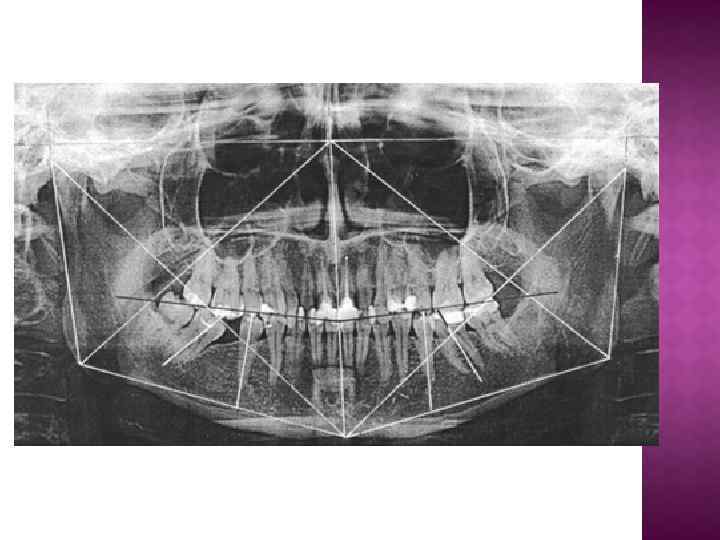

Нижний край орбиты. Вершина суставной ямки. Суставная головка нижней челюсти. Глазерова щель. Венечный отросток нижней челюсти. Передне-боковая стенка верхне-челюстной пазухи. Шиловидный отросток височной кости. Внутренний край ветви нижней челюсти. Нижне-челюстной канал. Угол нижней челюсти. Подбородочное отверстие нижне-челюстного канала. Подъязычная кость. Внутриносовая перегородка. Наружный слуховой проход. Скуловая дуга. Твердое небо. Скуловая кость. Крыловидный отросток клиновидной кости. Верхне-челюстной бугор. Дно верхне-челюстной пазухи.

I. Оценка качества рентгенограммы (контрастность, резкость, полнота охвата исследуемой области, проекционные искажения - удлинение, укорочение зубов, изменение формы и размеров челюстей).

II. Оценка окружающей костной ткани: 1) состояние межзубных перегородок (форма, высота, состояние замыкательной компактной пластинки, состояние кортикального слоя, степень минерализации и состояние губчастого вещества); 2) наличие перестройки впутрикостной структуры; анализ патологической тени (участка деструкции или остеосклероза) включает в себя определение локации, формы, размеров, характера контуров, интенсивности структуры различных отделов челюстей; 3) наличие ретинированных зубов (количество, локализация, положение в челюсти, групповая принадлежность, стадия формирования зуба, состояние фолликула); 4) оценка состояния височно-нижнечелюстного сустава (соотношение суставных головок и ямок, наличие патологических изменений); 5) состояние нижнечелюстных пазух (симметричность, наличие затемнения (локализация, площадь, интенсивность), резкость контуров кости, соотношение корней зубов к пазухе, состояние носовой перегородки (искривление); 6) состояние нижнечелюстного канала (локализация, соотношение корней зубов к каналу, наличие патологических элементов).

III. Определение объекта исследования. IV. Анализ тени зуба: 1) состояние коронки (наличие кариозной полости, пломбы, дефекта пломбы, соотношение дна кариозной полости к полости зуба); 2) характеристика полости зуба (наличие пломбировочного материала, дентиклей); 3) состояние корней (количество, форма, величина, контуры); 4) характеристика корневых каналов (ширина, направление, степень пломбирования); 5) оценка периодонтальной щели (равномерность, ширина, состояние компактной пластинки лунки - сохранена, истончена, утолщена).